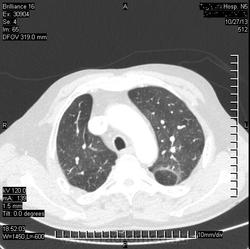

Коллега, а что, инфаркт искали? Или у Вас так окклюзии ЛА ищут? Интересно, а просто ОГК , для искл. пневмонии

( или инфаркт-пневмонии) слева?

Виноват. Не все вчера успел выложить.ТЭЛА.

ТЭЛА слева, я правильно вижу?

Да. Слева.